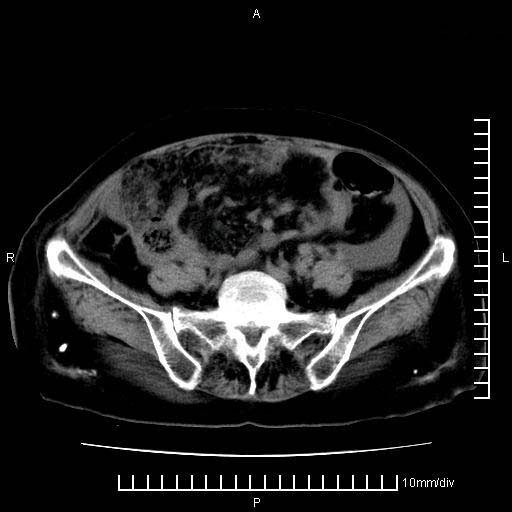

上腹疼痛月余,外院核磁诊断胰腺癌。现临床示右下腹可明显触及包块,可片子上怎么没有看到?

胰腺体部癌累及周围器官,腹膜、粘连,临床摸到的可能是粘的组织

1、考虑胰腺癌伴腹膜腔转移,胸腹水。

1)考虑胰腺癌并胰腺假性囊肿形成。2)肝内低密度灶,不排除转移。3)右肾盂积水。4)腹水。5)右侧胸腔积液并右肺下叶部分膨胀不全。

考虑胰腺ca伴腹膜腔转移、肝左叶转移、右肾积水。右胸腔积液。